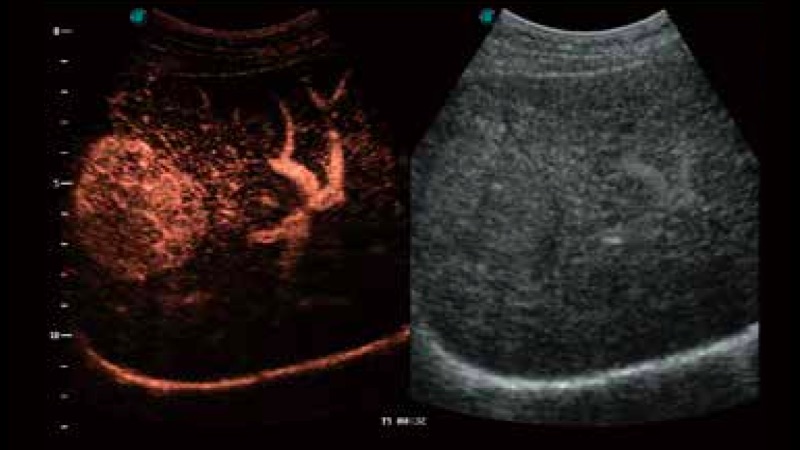

開立醫(yī)療通過不斷的技術(shù)創(chuàng)新,為大眾的生命健康提供持續(xù)關(guān)愛。P12 Plus采用全新一代超聲成像平臺,新平臺旨在將真實(shí)還原組織解剖結(jié)構(gòu)作為首要目標(biāo)。平臺采用全新集成化硬件模塊,搭載新一代芯片,系統(tǒng)性能得到大幅提升,為您的診斷提供了豐富的臨床信息。優(yōu)異的圖像表現(xiàn),豐富的探頭配置,全面的應(yīng)用功能,為您日常診斷提供了可靠的助手。

智影賦能基層診療

彩色多普勒超聲診斷系統(tǒng)